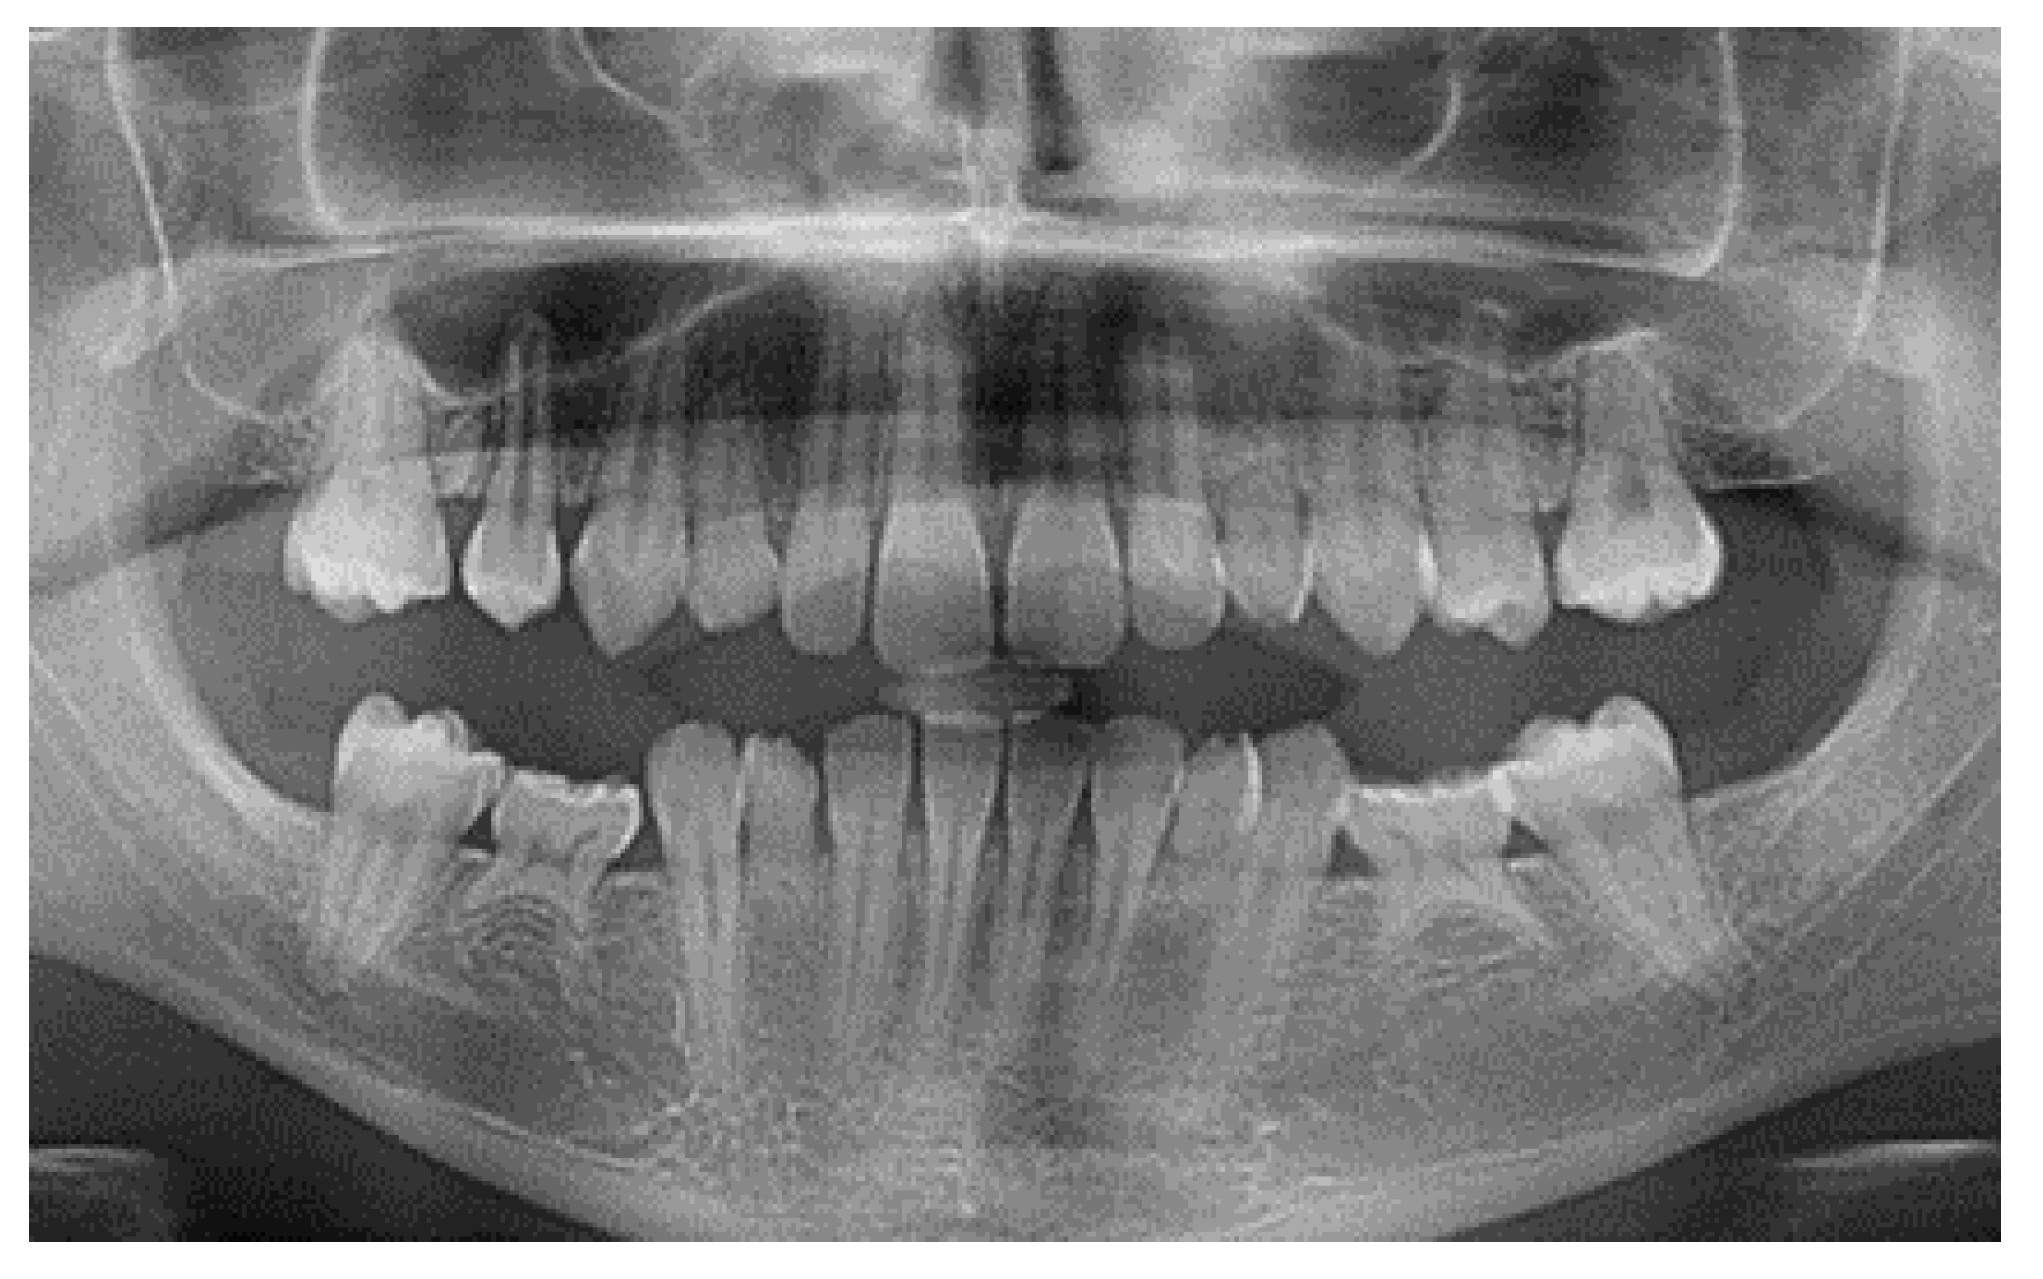

2.2. Patient Characteristics

2.5. Individual Cases Description

- Case 1:

- Case 2:

- Case 3:

- Case 4:

- Case 5:

| Patient | |||||

|---|---|---|---|---|---|

| 1 | 2 | 3 | 4 | 5 | |

| Gender | M | F | F | M | F |

| Age | 24 | 35 | 44 | 27 | 21 |

| Tooth agenesis | 35, 45 | 35, 45 | 35, 45 | 35, 45 | 35, 45, 14, 17, 24, 27, 44, 47, 34, 37 |

| Implant Type | BLT RC | BLT RC | BLT RC | #45: BLT RC #35: BL RC | #13, 23: BLT NC #35, 45: BL RC |

| Implant dimensions | #35: Ø4.1 × 10 #45: Ø4.1 × 10 | #35: Ø4.1 × 10 #45: Ø4.1 × 10 | #35: Ø4.1 × 10 #45: Ø4.1 × 10 | #35: Ø4.1 × 10 #45: Ø4.1 × 10 | #13, 23: Ø3.3 × 12 #35, 45: Ø4.1 × 10 |

| Insertion Torque [N/cm] | #35: 33 #45: 30 | #35: 45 #45: 40 | #35: 36 #45: 39 | #35: 35 #45: 37 | #13: 35, #23: 38 #35: 40, #45: 40 |